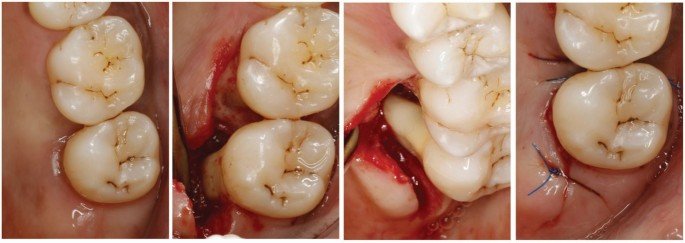

Cas Cliniques Commentés

Cas 1 — Découverte fortuite lors du bilan parodontal initial

Patient : Homme, 42 ans, fumeur modéré (8 cigarettes/jour), sans pathologie systémique connue. Consulte pour bilan bucco-dentaire de routine. Aucune douleur spontanée.

Problématique identifiée : Lors du sondage parodontal systématique à la sonde de Nabers, pénétration de 4 mm en vestibulaire de la 36 (première molaire mandibulaire gauche). L’OPG est peu contributif. Le cliché rétro-alvéolaire révèle une légère raréfaction osseuse interradiculaire. Diagnostic : atteinte de furcation classe II de Hamp, sous-classe B de Tarnow & Fletcher. Tests de vitalité positifs.

Prise en charge : Phase étiologique initiale (motivation à l’hygiène, détartrage-surfaçage sous anesthésie locale de la 36). Arrêt tabagique fortement conseillé.

Évolution attendue : Réévaluation à 8-12 semaines. En cas de résidu de poche > 4 mm après phase étiologique bien conduite, indication de chirurgie d’accès envisagée. Le tabagisme représente un facteur de risque majeur limitant la cicatrisation.

Point pédagogique : Une lésion de classe II peut être stabilisée par la thérapeutique étiologique seule si le patient adopte une hygiène rigoureuse. Le sondage de Nabers est ici l’outil diagnostique décisif — ni l’examen visuel ni l’OPG n’auraient permis ce diagnostic.